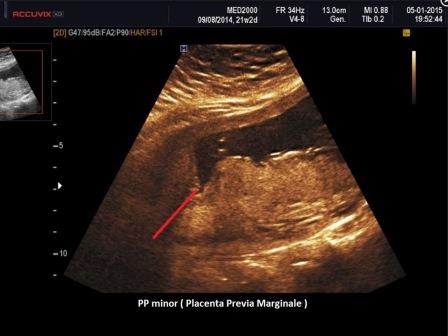

La Placenta previa consiste in un impianto anomalo della placenta: si definisce previa una placenta che nel corso del terzo trimestre si trova localizzata nel segmento inferiore ed è quindi previa nei confronti del feto. La diagnosi definitiva deve essere posta solo dopo la 32a settimana di gestazione preferibilmente con metodica transvaginale.

La Placenta Previa (PP) è classificata ecograficamente a seconda della rilevanza clinica (RCOG 2011 ): se la placenta ricopre interamente l'Orifizio Uterino Interno (OUI) viene considerata PP major (ex PP centrale completa e parziale);

se il bordo placentare si inserisce sul Segmento Uterino Inferiore ma non ricopre l'OUI ed il bordo placentare dista < 2 cm. dall'OUI si parla allora di PP minor (ex PP marginale);